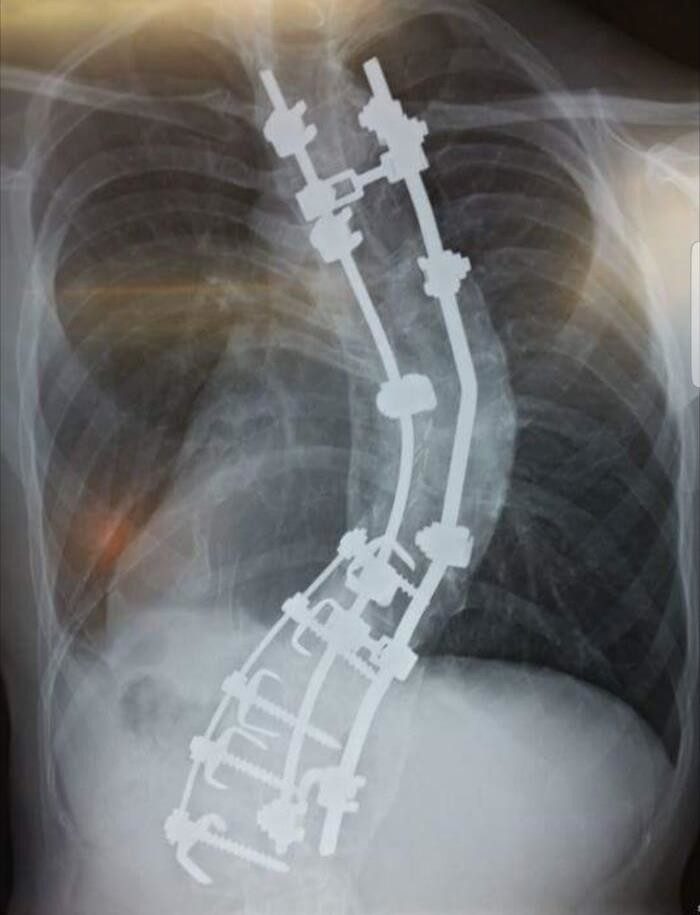

24. «Мой позвоночник. Мой рост был 178 см, когда я ложился под нож, теперь мой рост 188 см. А изначально должен был быть 2 метра»